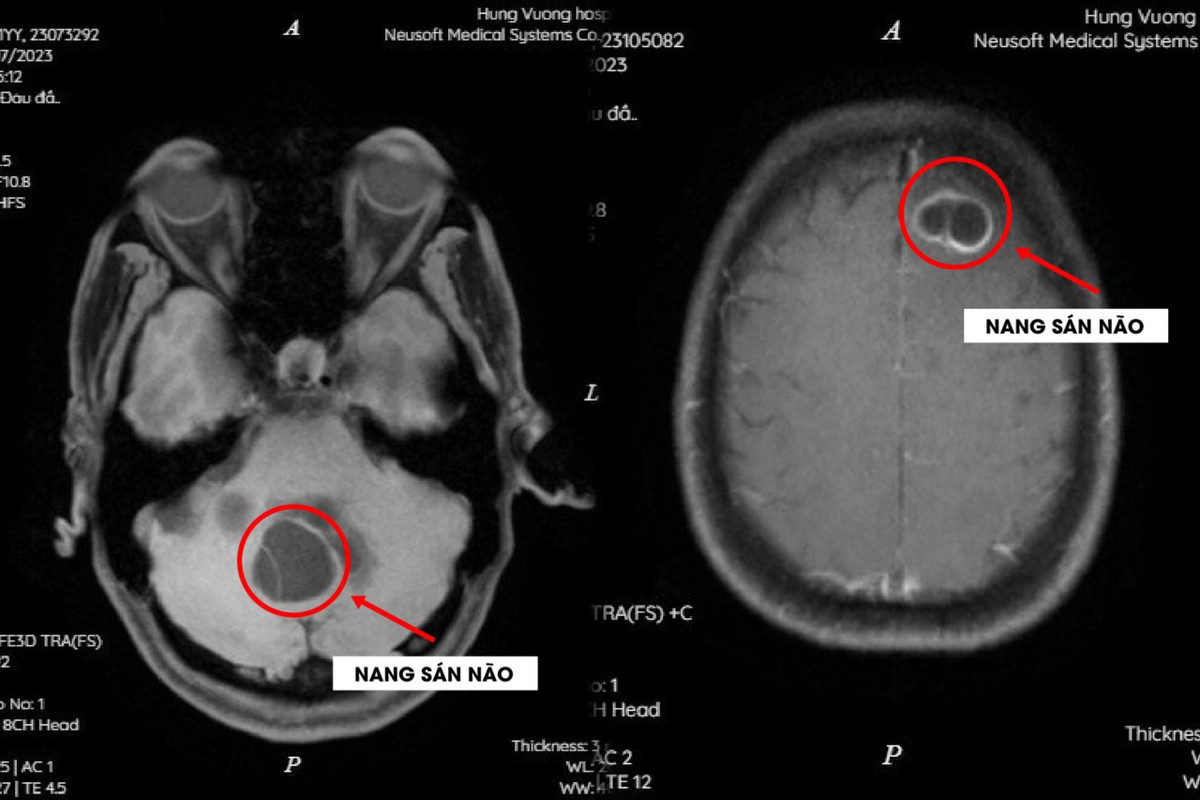

Hình ảnh sán làm tổ trong não của hai bệnh nhân. (Ảnh: BVCC)

Ngày 30/11, các bác sĩ khoa Nội Tổng hợp - Bệnh viện Đa khoa Hùng Vương cho biết, bệnh nhân đi khám vì đau đầu âm ỉ, mệt mỏi, chán ăn, sụt cân kéo dài. Kết quả chụp MRI sọ não phát hiện tổn thương dạng nang trong nhu mô não, dương tính với sán dây chó (Echinococus).

Các bác sĩ chẩn đoán cả hai bệnh nhân bị nang sán não (cerebral hydatid cysts) do sán dây chó (Echinococus).